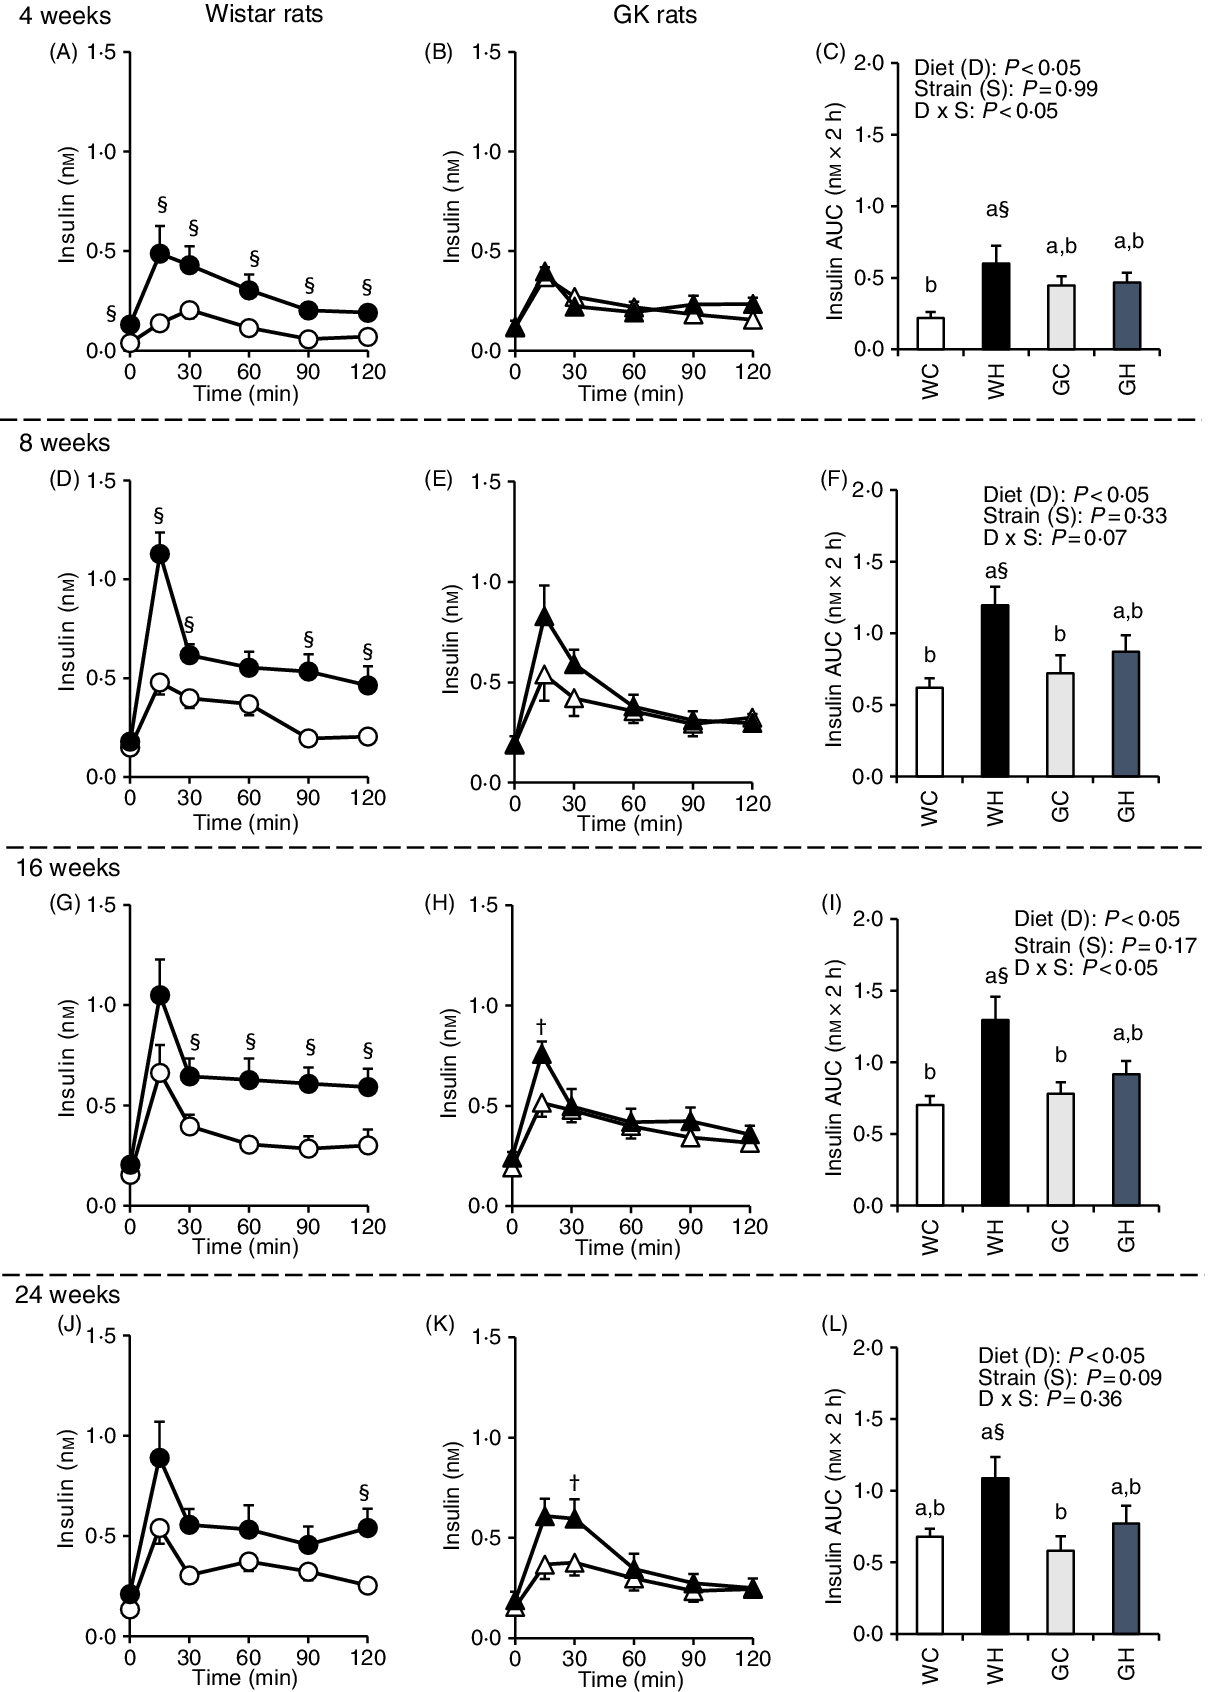

Postprandial insulin response

Insulin secretion was immediately increased (peaked at 15 or 30 min) after the administration of liquid diet in all groups. In the WH group, insulin concentrations at multiple time points (Fig. 2(A), (D), (G) and (J)) and the AUC were higher compared with those in the WC group throughout experimental period (Fig. 2(C), (F), (I) and (L)). In contrast, the GH group had higher insulin concentrations only at 15 min after 16 weeks and 30 min after 24 weeks, compared with those of the GC group (Fig. 2(H) and (K)). However, no significant differences were observed in the AUC between the GC and GK groups throughout the experimental period (Fig. 2(C), (F), (I) and (L)).

Fig. 2. Postprandial insulin responses under meal tolerance test (MTT) after 4-, 8-, 16- and 24-week feeding period. Wistar and diabetic Goto-Kakizaki (GK) rats were fed either a control diet or high-fat/high-sucrose (HFS) diet for 4, 8, 16 and 24 weeks before conducting MTT. After an overnight fast, blood samples were collected from the tail vein before (0 min) and after oral administration of a liquid diet (Ensure H, 10 ml/kg body weight). ![]() , Wistar rats fed the control diet (WC);

, Wistar rats fed the control diet (WC); ![]() , Wistar rats fed the HFS diet (WH);

, Wistar rats fed the HFS diet (WH); ![]() , GK rats fed the control diet (GC);

, GK rats fed the control diet (GC); ![]() , GK rats fed the HFS diet (GH). Data are mean values with their standard errors (n 6–9 rats in each group). a,b Mean values with unlike letters are significantly different (P < 0·05, Tukey–Kramer’s test). § Significant differences between mean values of the WC and WH groups; † significant differences between mean values of the GC and GH groups (P < 0·05, Student’s t test). P values of two-way ANOVA for diet, strain and strain-by-diet interactions are shown in the panels.

, GK rats fed the HFS diet (GH). Data are mean values with their standard errors (n 6–9 rats in each group). a,b Mean values with unlike letters are significantly different (P < 0·05, Tukey–Kramer’s test). § Significant differences between mean values of the WC and WH groups; † significant differences between mean values of the GC and GH groups (P < 0·05, Student’s t test). P values of two-way ANOVA for diet, strain and strain-by-diet interactions are shown in the panels.